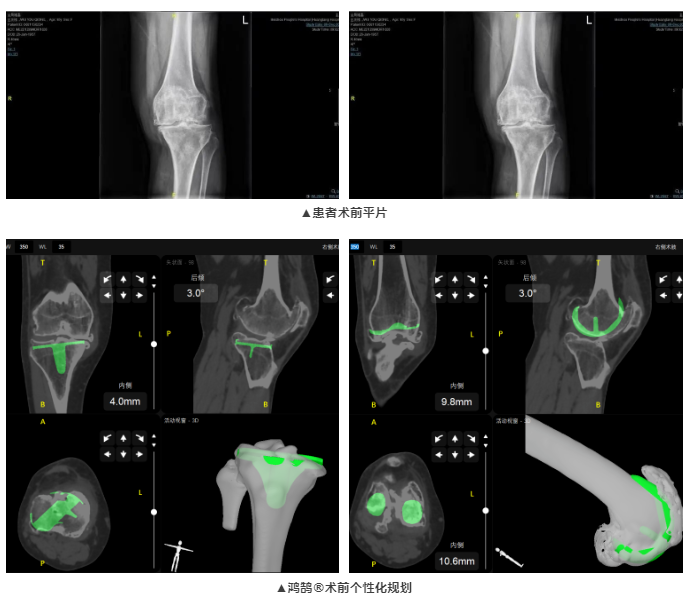

患者為65歲女性,雙膝疼痛20年,近日疼痛加劇,就診于梅州市人民醫(yī)院。術前經(jīng)檢查發(fā)現(xiàn)雙膝關節(jié)內翻畸形,診斷為雙膝關節(jié)骨性關節(jié)炎。術前患者雙膝疼痛,導致行走功能受到明顯阻礙,嚴重影響生活質量。廖紅興博士團隊經(jīng)綜合評估,決定行鴻鵠?骨科手術機器人輔助全膝關節(jié)置換術。

本次全膝關節(jié)置換術,術前,廖紅興博士團隊通過鴻鵠?為患者進行膝關節(jié)CT圖像三維重建,制定符合患者生理特征的個性化假體安裝方案,提高后續(xù)手術治療效率;術中,鴻鵠?引導完成機械臂注冊和骨注冊,機械臂精準定位到預期規(guī)劃位置,一體化截骨工具輔助醫(yī)生完成股骨脛骨截骨,進而實現(xiàn)假體精確安放。